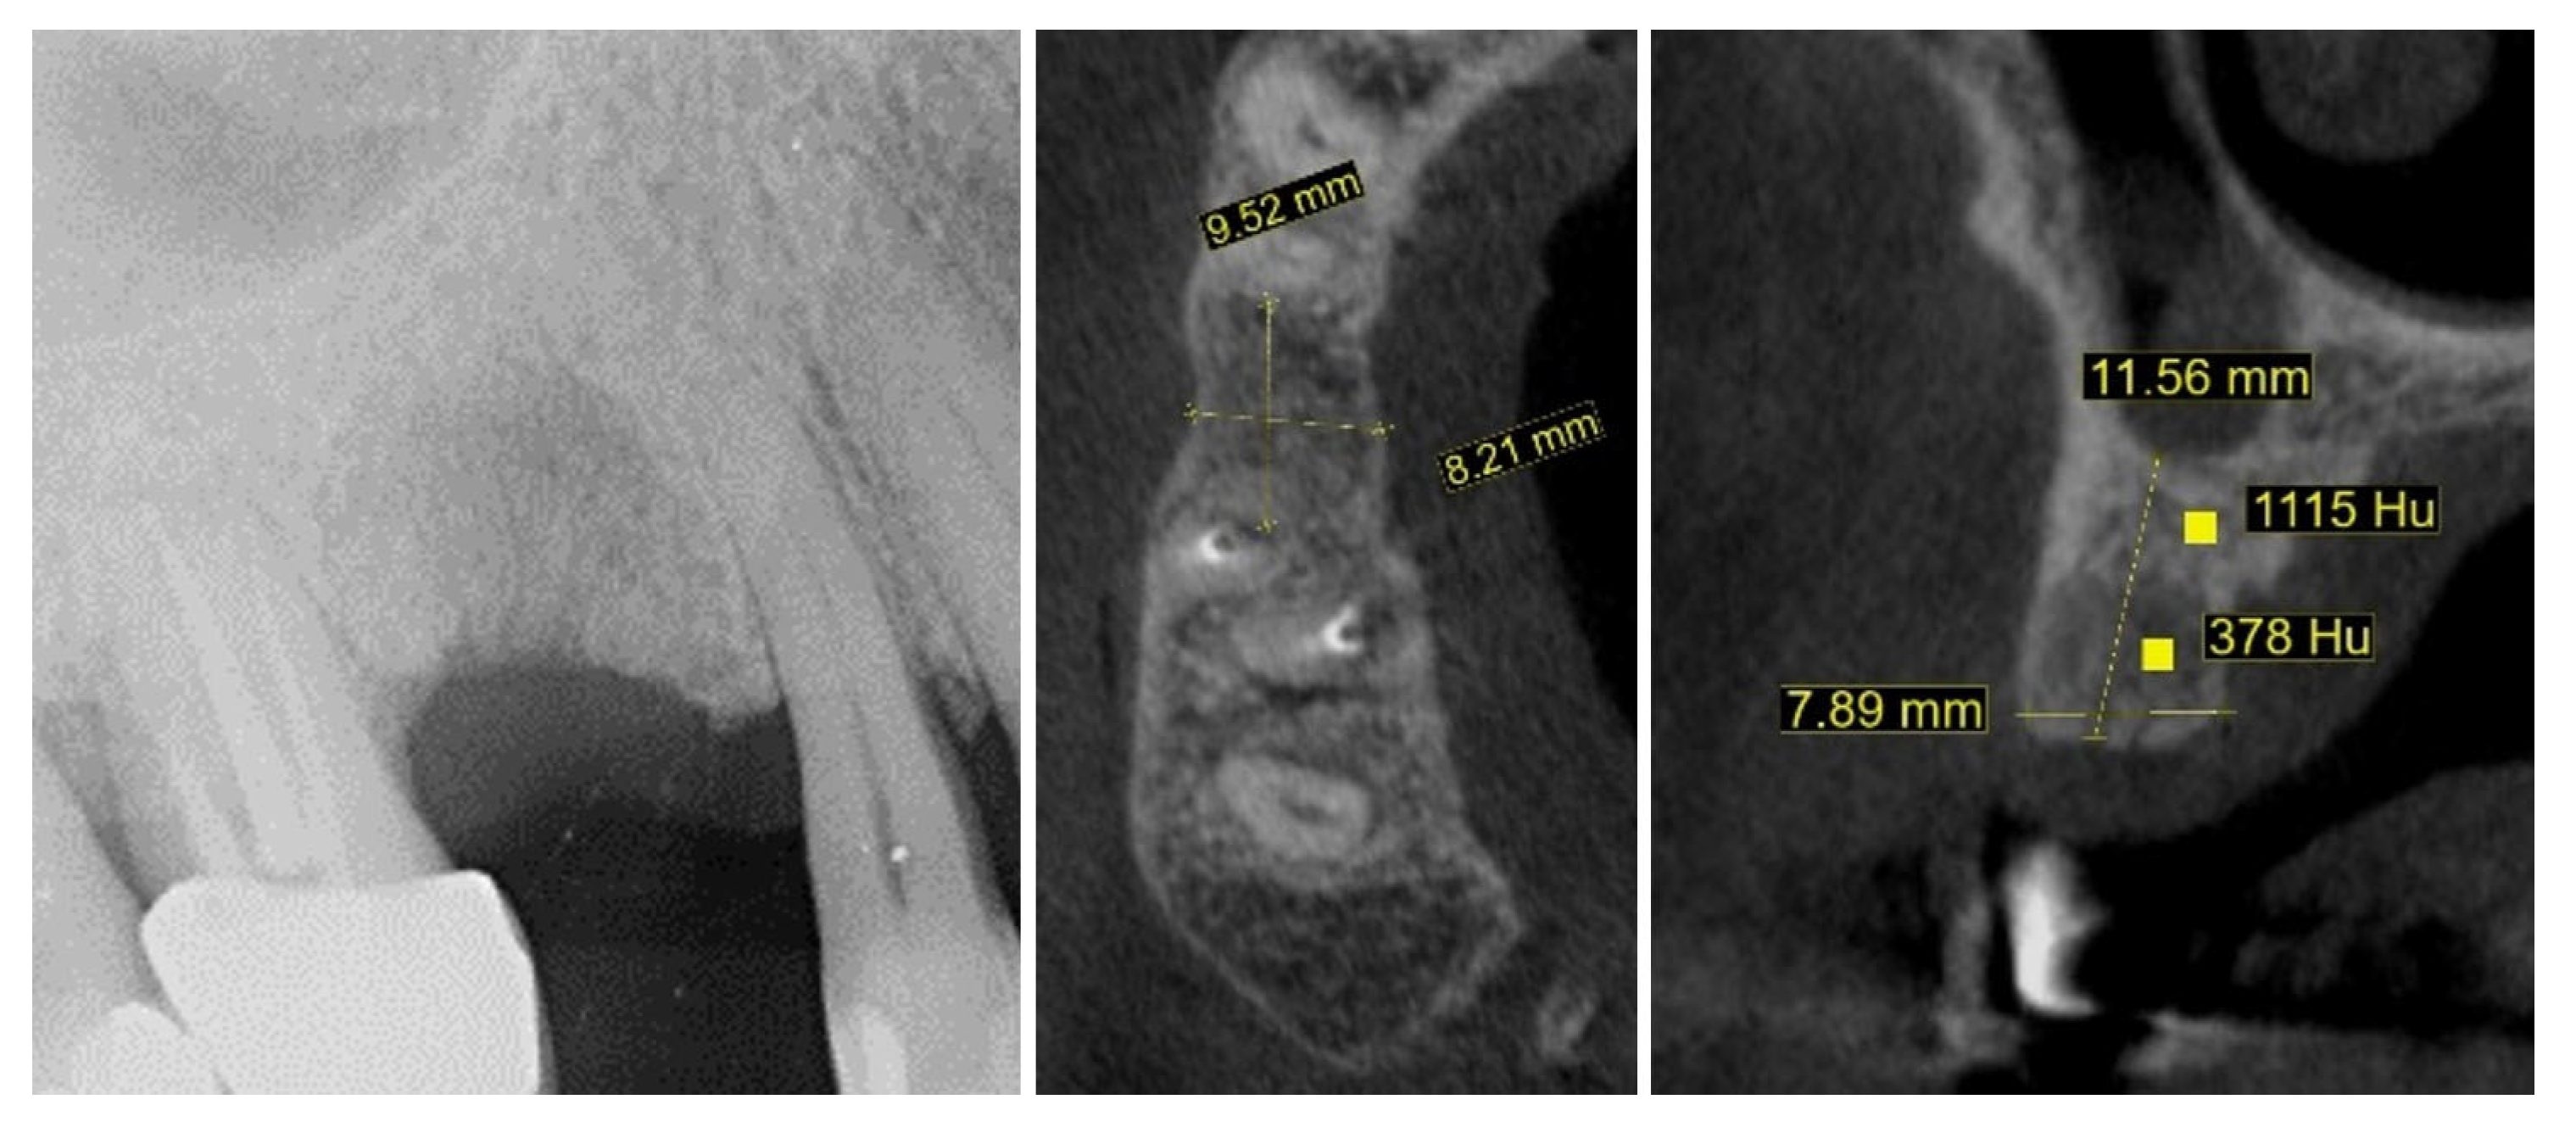

2. Materials and Methods—Clinical Case